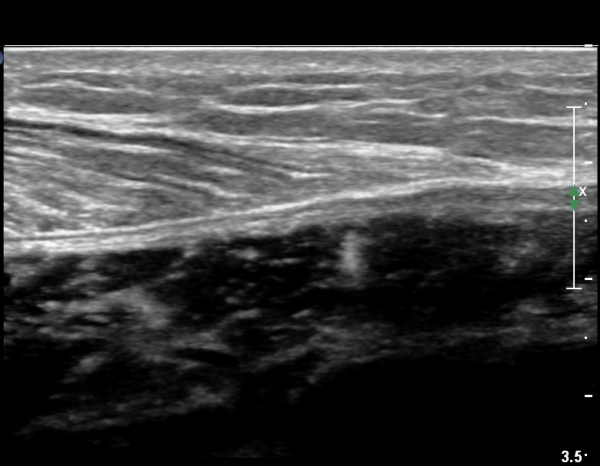

ºñº¹±Ù Á¾´Ü¸é°Ë»ç¿¡¼ ƯÀÌ ¼Ò°ßÀ» º¸ÀÌÁö ¾ÊÀ½(»çÁø 1).